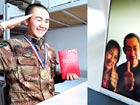

NO.1 类风湿关节炎(RA)

目前认为是与遗传、性激素、感染等因素相关的以关节滑膜为主要靶组织的全身性慢性自身免疫病。其主要诊断策略依赖临床表现(美国风湿病学学会类风湿关节炎分类标准)、自身抗体(ESR、CRP、ANAs等)及影像学(关节X线片)改变。

图为类风湿关节炎X线表现及发生机制

消化系统改变:颞颌关节炎(咀嚼障碍、疼痛、肿胀)、食管运动障碍(中下段蠕动减弱、食管下括约肌压力降低、胸骨后灼痛、吞咽困难)、缺血性胆囊炎(血管炎相关)、缺血性阑尾炎(血管炎相关)、肠道溃疡、全结肠炎、肠梗塞及药物相关性胃肠不适(抗类风湿药物,如NSAID等)。

另有肝损伤(鸟氨酸甲酰胺转移酶、γ-谷氨酰转肽酶升高)、胰腺外分泌功能障碍(亚临床型,血浆胰酶水平可正常)等。